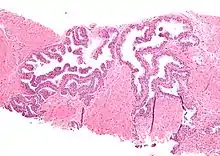

Histopathology of high-grade prostatic intraepithelial neoplasia (HGPIN) with typical features, H&E stain.[6]

High-grade prostatic intraepithelial neoplasia.

HGPIN typically has one of four different histologic patterns:[2]

Several architectural variants of PIN have been described, and many cases have multiple patterns. The main ones are tufting, micropapillary, cribriform, and flat. Although these different appearances may cause confusion with other conditions, they have not been found to be of clinical importance. Rarer types are signet-ring-cell, small-cell-neuroendocrine, mucinous, foamy, inverted, and with squamous differentiation.[3]